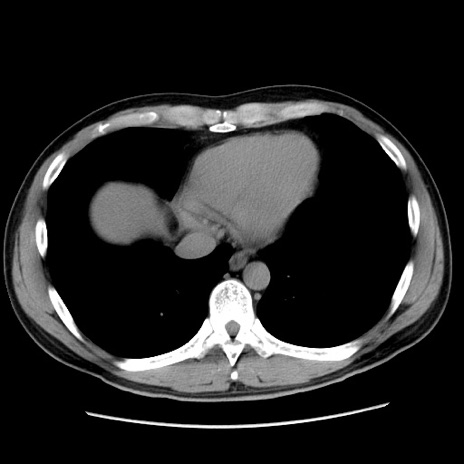

冠状断像

【症例】20歳代 男性

【主訴】心窩部痛

【現病歴】今朝より上腹部痛あり。一旦軽快していたが再度出現したため救急要請。昨日夕に白身の魚を含む刺身を食べた。

【身体所見】BP 136/89mmHg、HR 74/min、BT 37.0℃、腹部:膨満、軟、心窩部に圧痛あり。反跳痛なし、筋性防御なし、腸雑音やや亢進あり。

【データ】WBC 17700、CRP 0.48